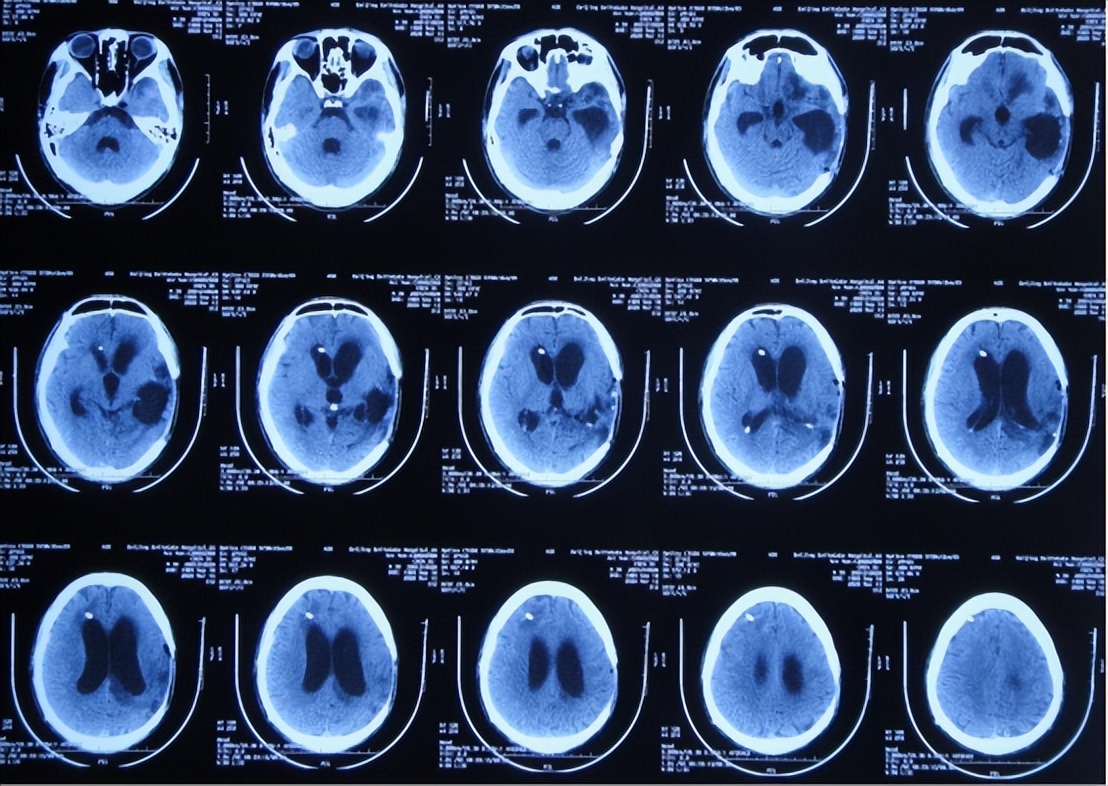

对所有的静脉rt-PA溶栓患者均常规在溶栓治疗后的24小时进行头颅CT影像学检查以 明确有无出血转化,或在静脉rt-PA溶栓治疗过程中或静脉溶栓后24小时内患者 出现临床症状加重(如:意识障碍加深加重

肢体肌力较溶栓前进一步明显下 降、语言功能较溶栓前进一步恶化、出现异常烦躁不安、剧烈或较剧烈的头痛、 频繁较频繁的恶心呕吐等)怀疑有继发性脑出血时则立即对其进行头颅CT检查, 以明确有无HT的发生。

HT可分为症状性颅内出血及无症状性颅内出血。溶栓治疗后s ICH的分类通常基于两个 主要因素:出血的影像学表现和相关神经功能恶化的存在。

而溶栓后HT的影像学分类传统上则区分为出血性梗死和脑实质血肿,前者代表梗死区域的点状出血,后者代表有或无占位效应的边界清楚的出血区域。